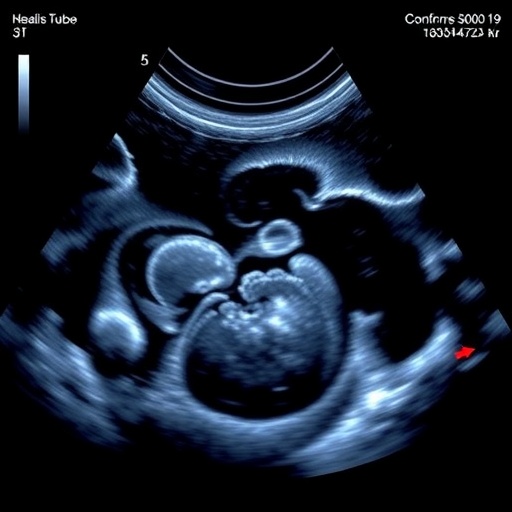

Ultrasonography leverages sound waves to delineate soft tissues in real time, allowing clinicians to visualize the endotracheal tube as it traverses the trachea. This technique stands apart from static radiology by furnishing dynamic imaging during the intubation process itself, enhancing the chances of immediate correction if misplacement occurs. The data synthesized through this meta-analysis elucidate the high sensitivity and specificity of tracheal ultrasound, underscoring its reliability and potential to supplant traditional confirmation tools, especially in resource-limited or time-sensitive settings.

Technological advancements have also refined the ultrasound equipment and probes tailored specifically for neonatal anatomy, optimizing image resolution while adhering to safety parameters. Portable machines equipped with high-frequency linear transducers facilitate succinct imaging of the fetal neck and tracheal structures without undue neonatal handling or repositioning, reducing procedural stress. The ease of sterilization and cost-effectiveness further bolster the feasibility of widespread adoption, making this tool an attractive asset for NICUs globally.